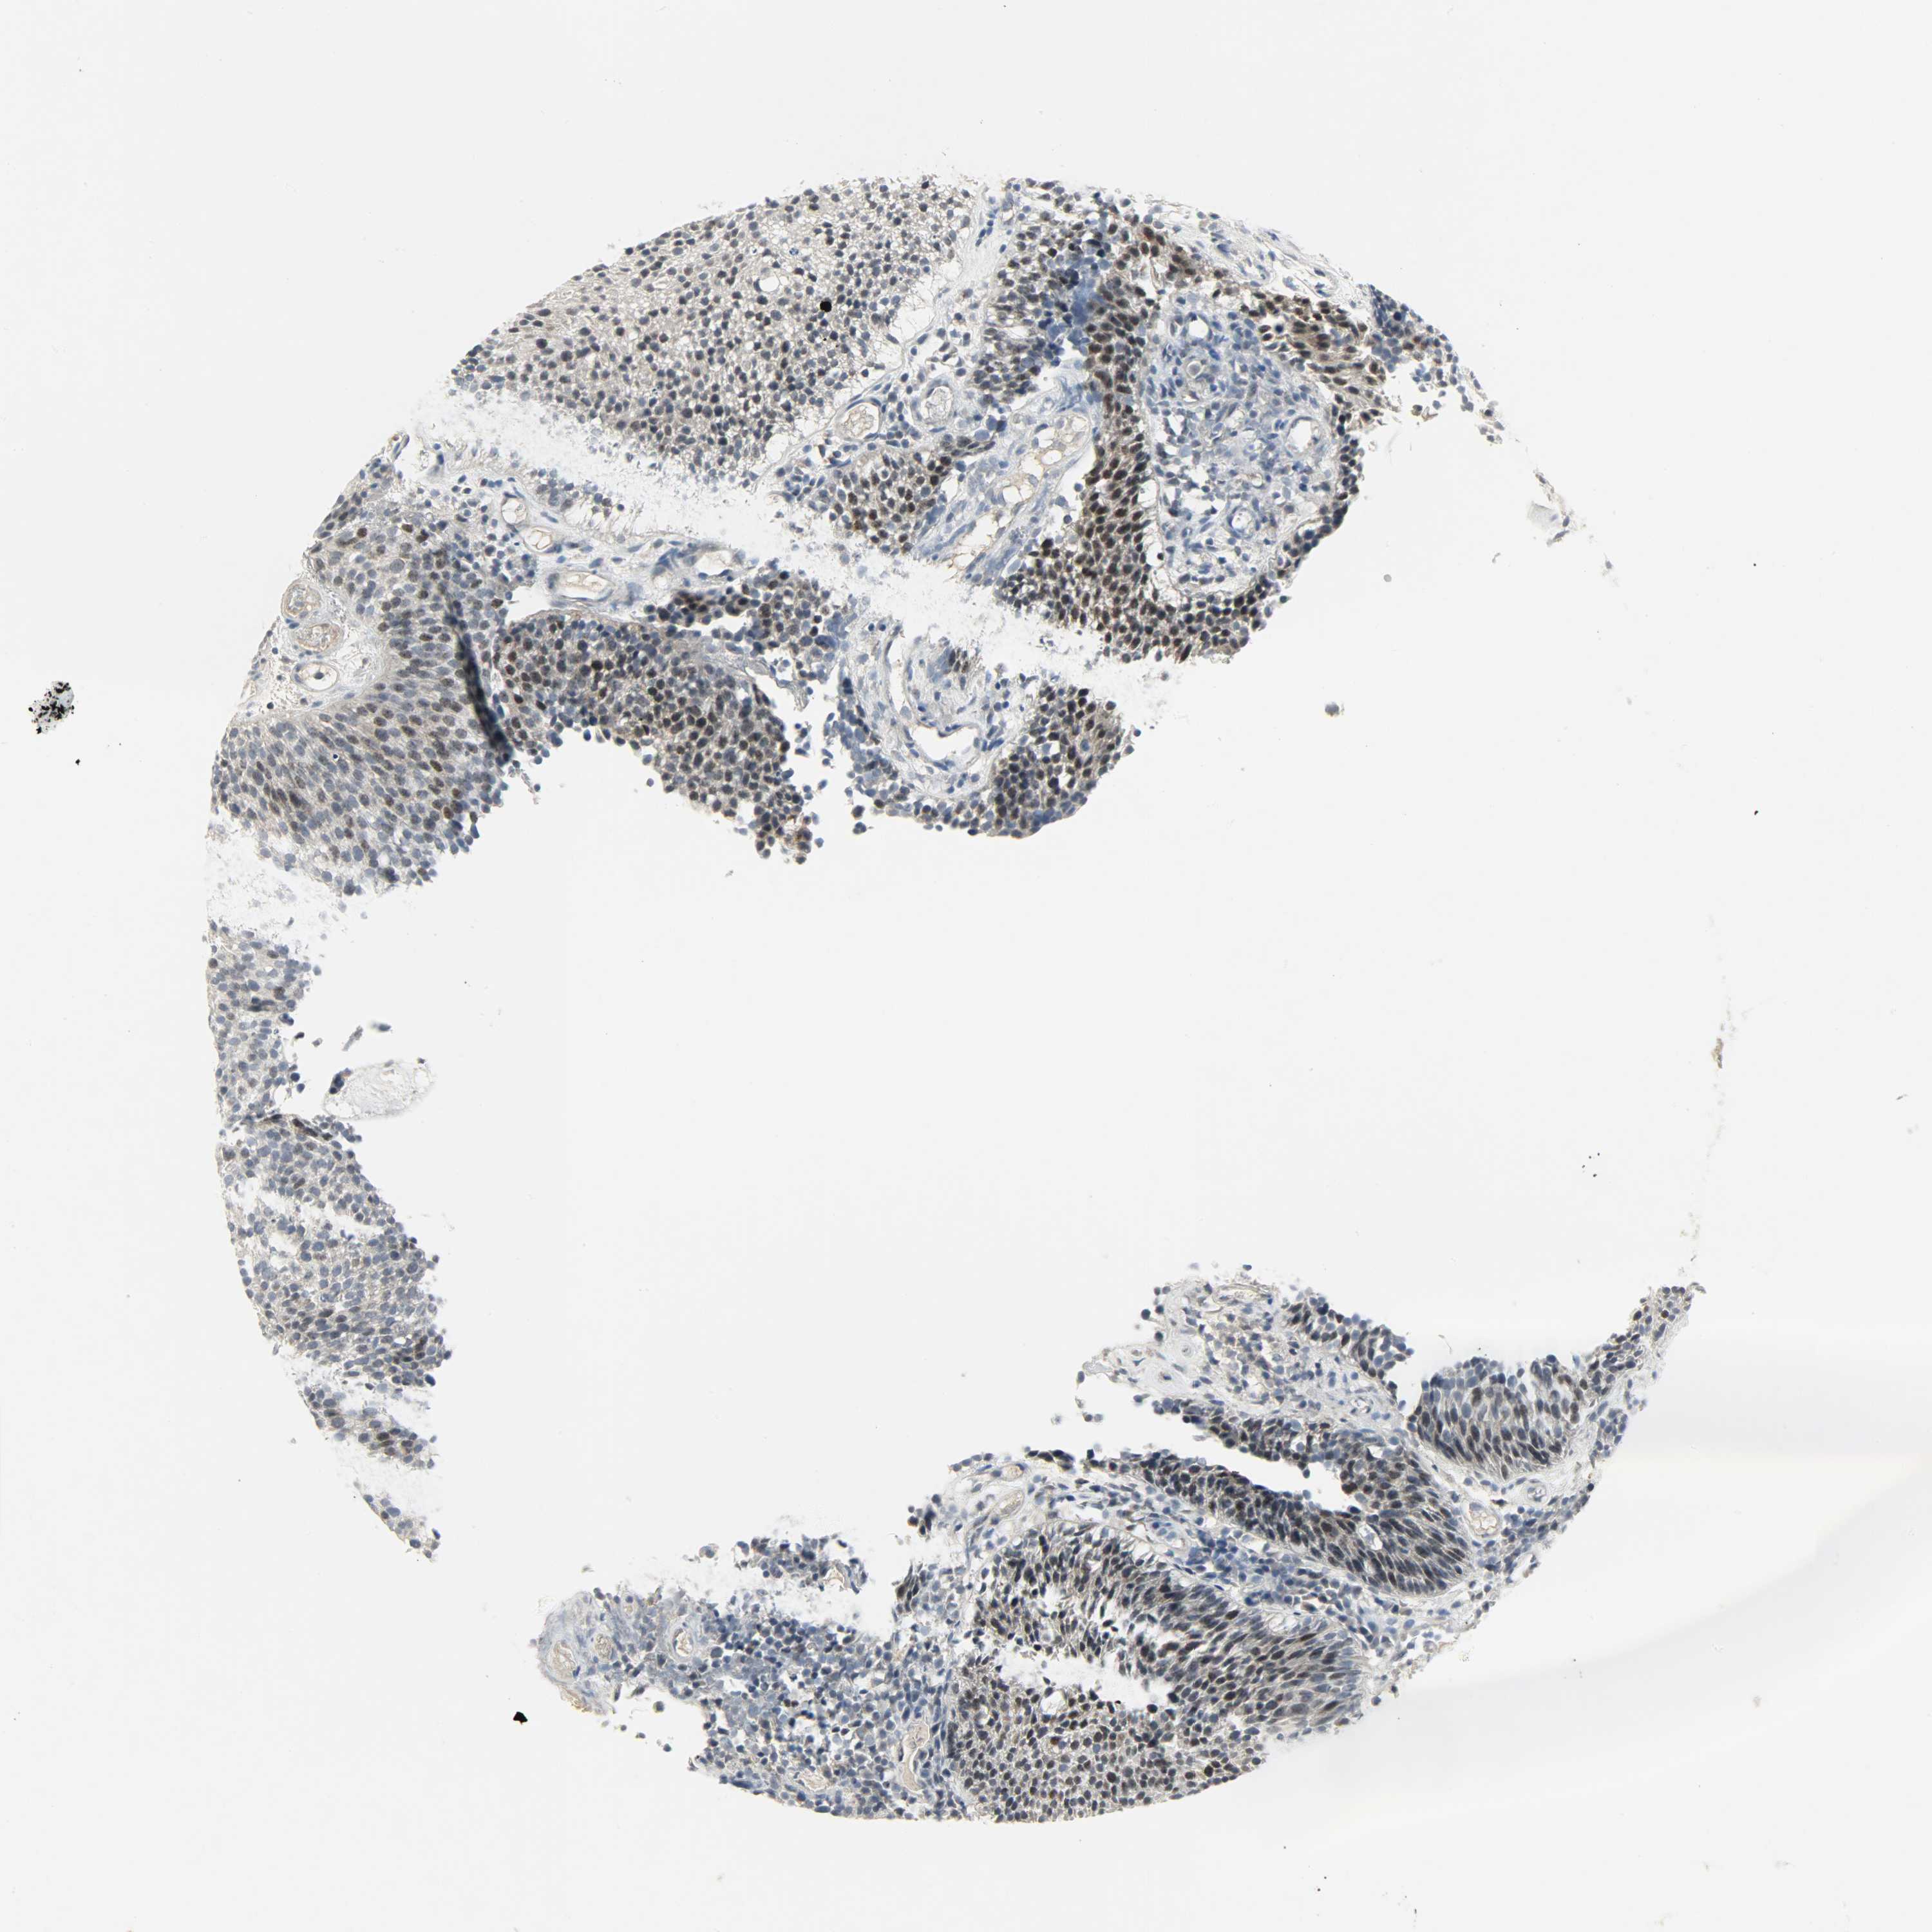

UROTHELIAL CANCER - Protein expressioni

A mouse-over function shows sample information and annotation data. Click on an image to view it in a full screen mode. Samples can be filtered based on level of antibody staining by selecting one or several of the following categories: high, medium, low and not detected. The assay and annotation is described here.

Antibody stainingi

Antibody staining in the annotated cell types in the current human tissue is reported as not detected, low, medium, or high, based on conventional immunohistochemistry profiling in selected tissues. This score is based on the combination of the staining intensity and fraction of stained cells.

Each image is clickable and will lead to virtual microscopy that enables deeper exploration of all samples and also displays staining intensity scores, fraction scores and subcellular localization as well as patient and tissue information for each sample.

Antibody HPA017206

Urothelial carcinoma, Low grade

Urothelial carcinoma, High grade